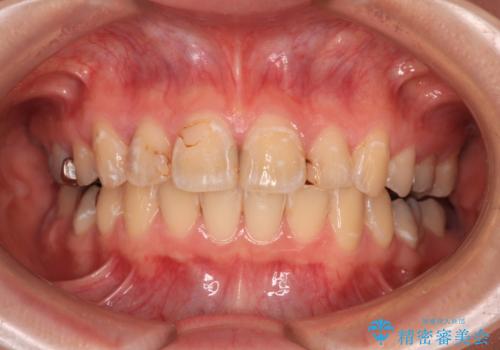

- 上の前歯の出っ歯とでこぼこの歯並びを気にして来院された患者様です。

上下顎歯列ともに前方に突出していましたが、上顎歯列がより前方位にあったため、上顎左右は第1小臼歯を、下顎左右は第二小臼歯を抜歯することとしました。

目立たないワイヤー装置にて抜歯矯正を行うこととしました。

下顎は過剰歯が埋伏しており、それが原因となってスペースが閉じなかったため、途中で抜歯して速やかに仕上げました。